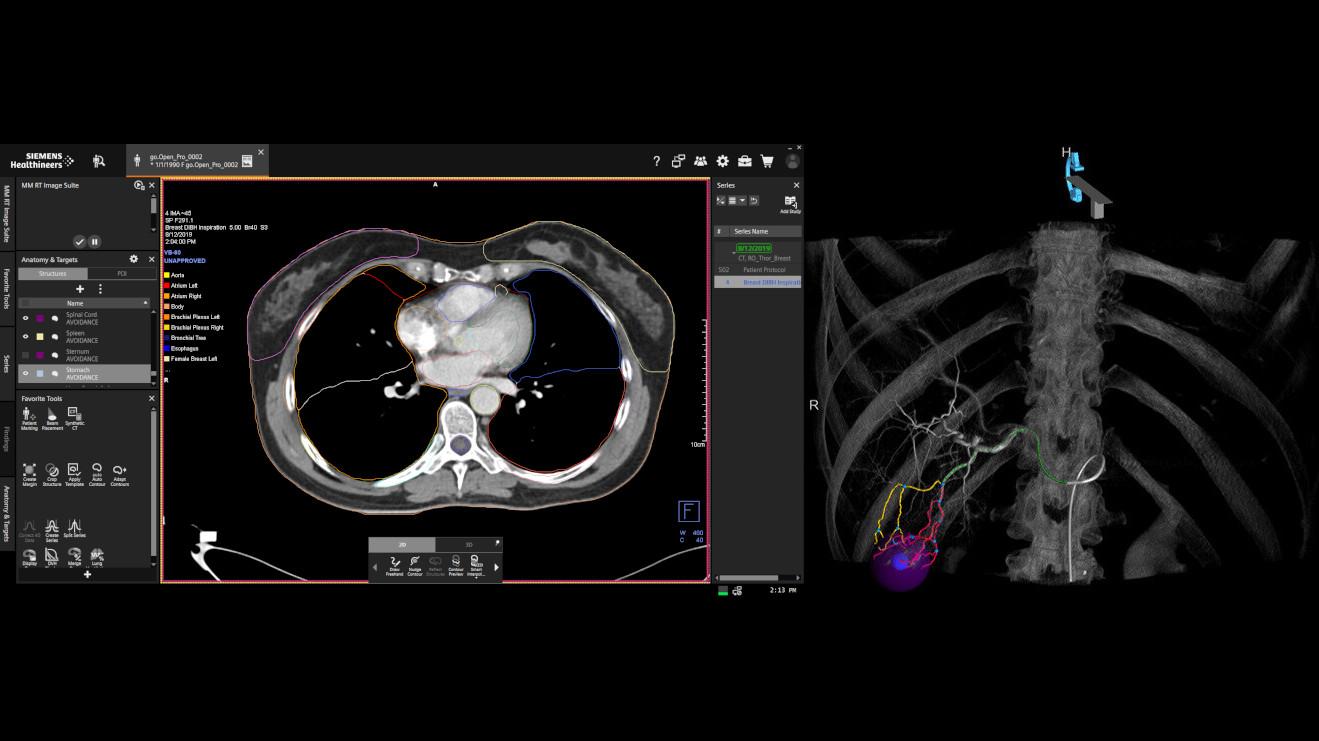

Treatment Planning

- MRI / CT

- PET-CT / SPECT

- Radiation Oncology

Our mission has evolved beyond merely developing new medical devices to delivering end-to-end, intelligent solutions to better support our customers. Shaping the future of cancer care with integrated, connected care pathways designed to drive efficiencies and deliver world-class diagnosis and treatment. Because we are committed to both your success and the health of your patients. Together with Varian, we aim to realize our vision of a world without fear of cancer.